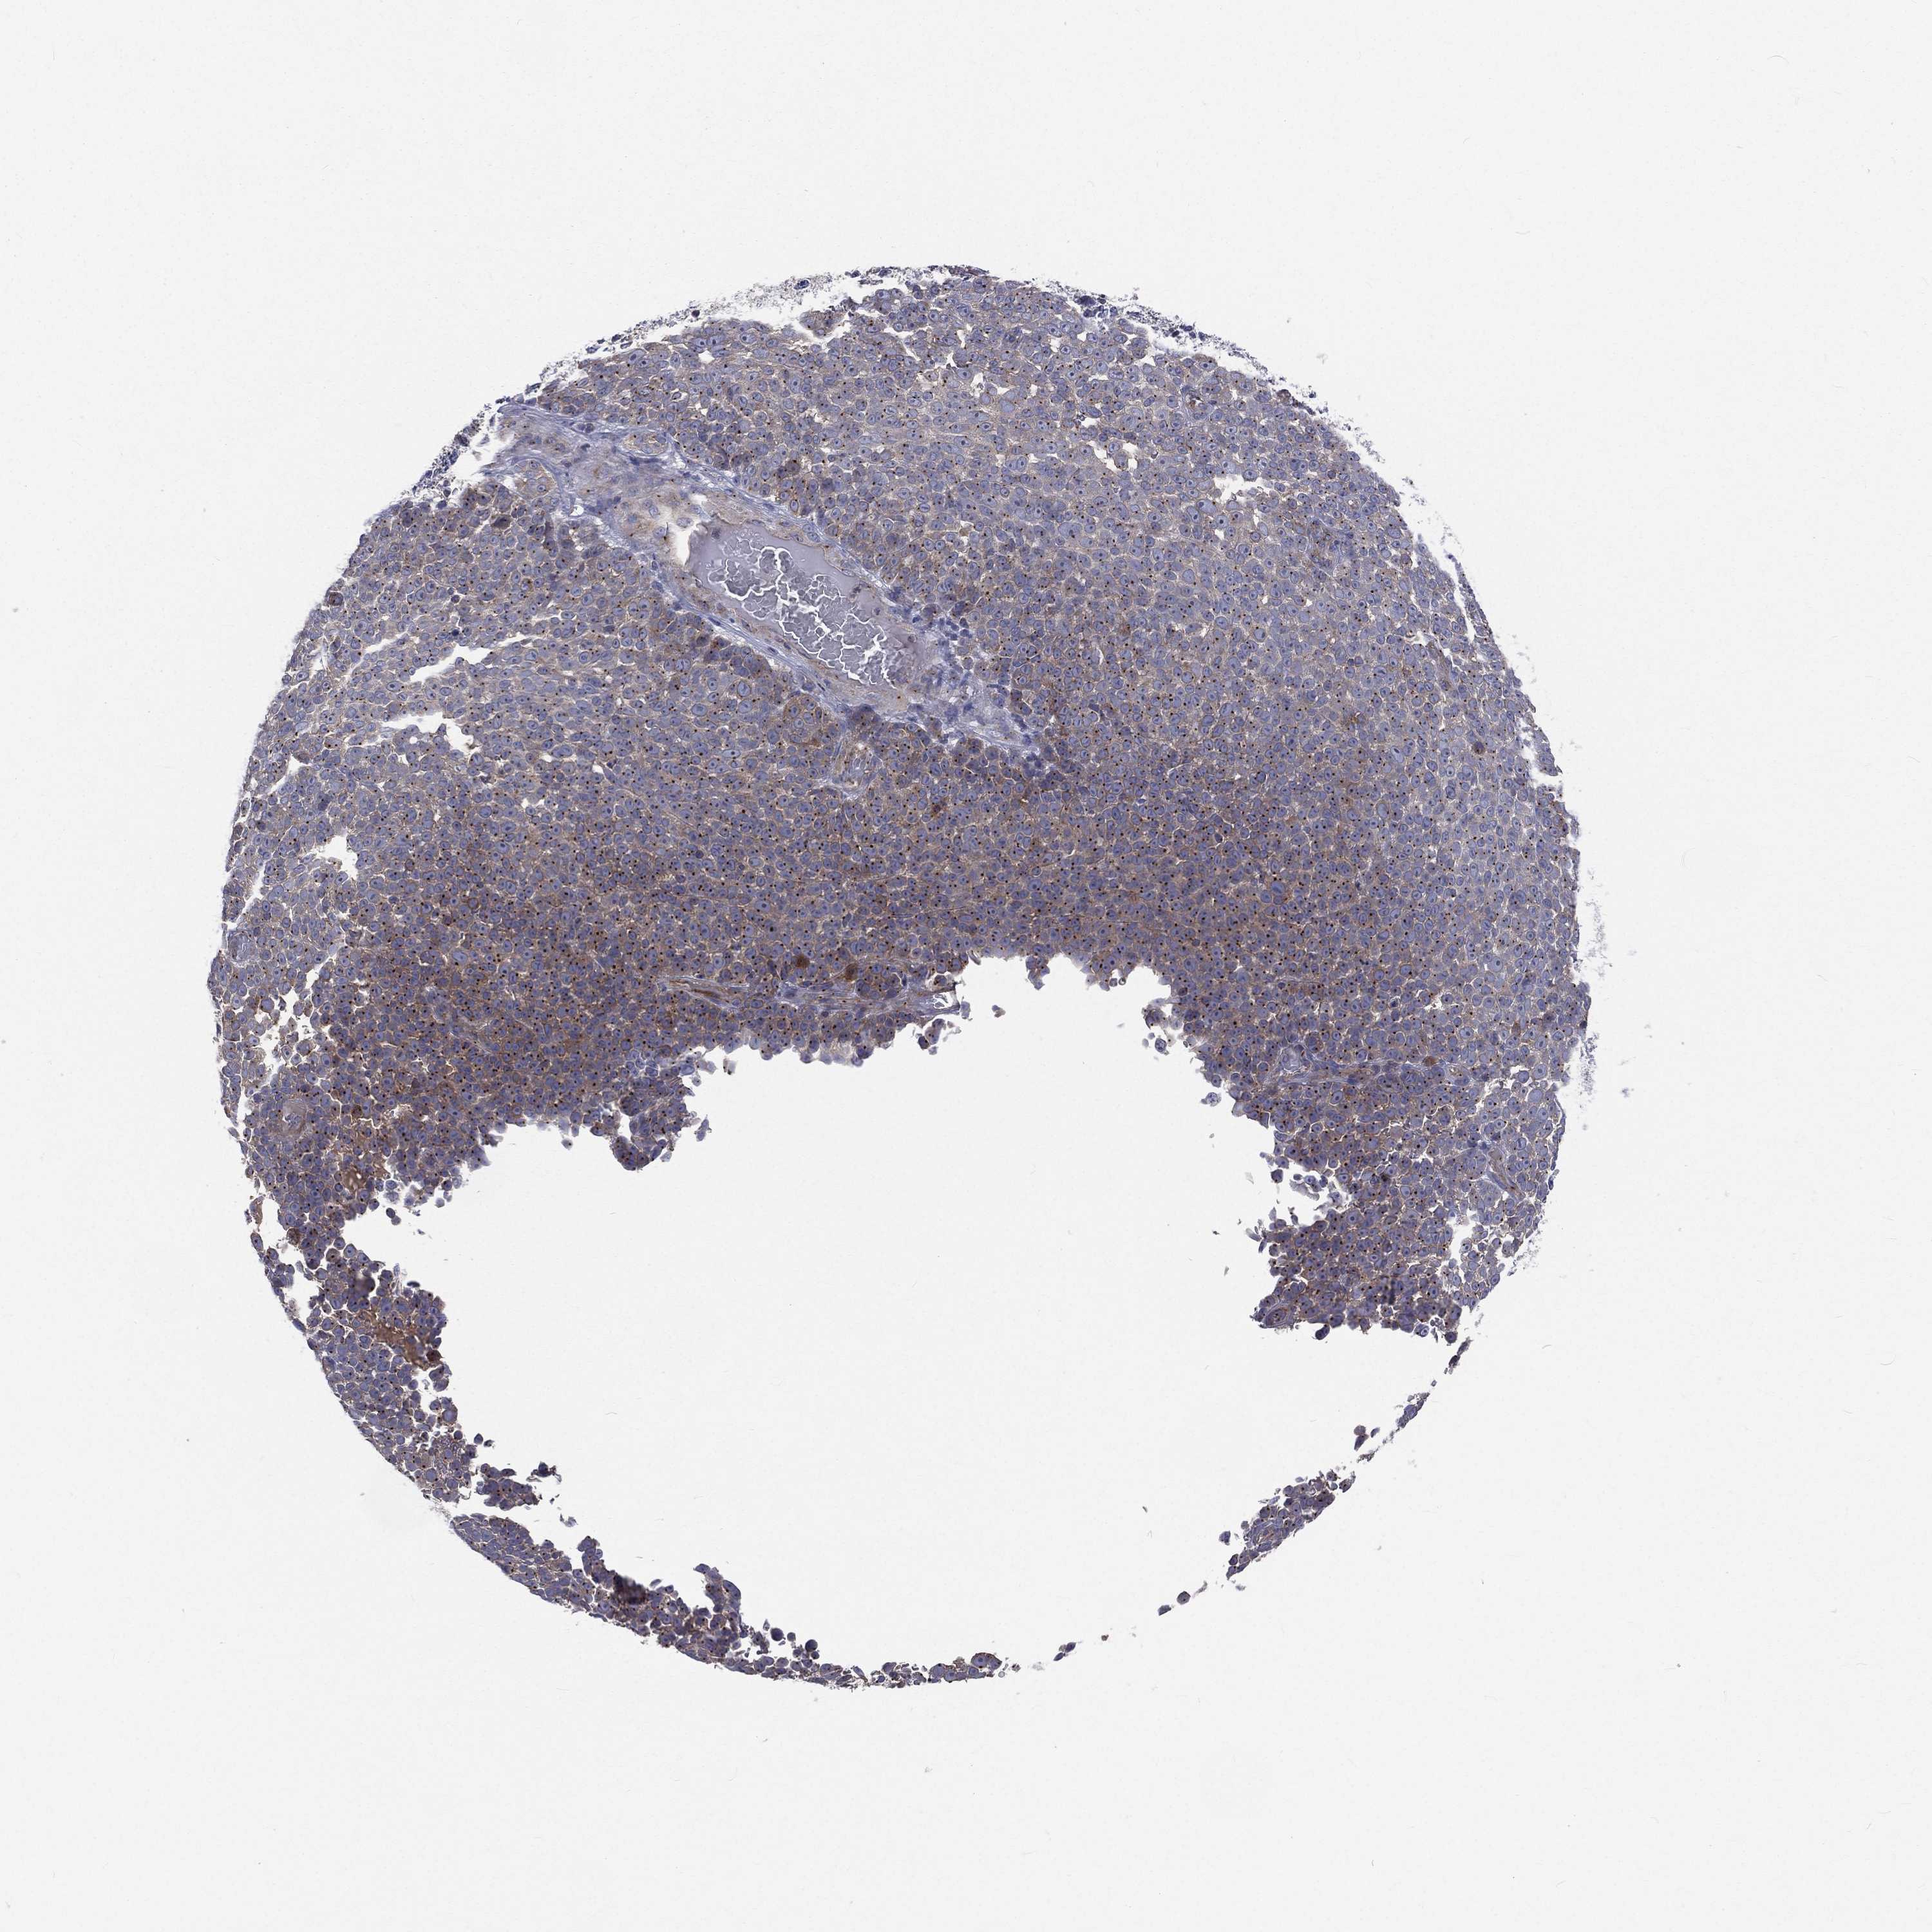

MELANOMA - Protein expressioni

A mouse-over function shows sample information and annotation data. Click on an image to view it in a full screen mode. Samples can be filtered based on level of antibody staining by selecting one or several of the following categories: high, medium, low and not detected. The assay and annotation is described here.

Note that samples used for immunohistochemistry by the Human Protein Atlas do not correspond to samples in the TCGA dataset.

Antibody stainingi

Antibody staining in the annotated cell types in the current human tissue is reported as not detected, low, medium, or high, based on conventional immunohistochemistry profiling in selected tissues. This score is based on the combination of the staining intensity and fraction of stained cells.

Each image is clickable and will lead to virtual microscopy that enables deeper exploration of all samples and also displays staining intensity scores, fraction scores and subcellular localization as well as patient and tissue information for each sample.

Antibody HPA021191

Antibody HPA021762

Malignant melanoma, NOS

Malignant melanoma, Metastatic site